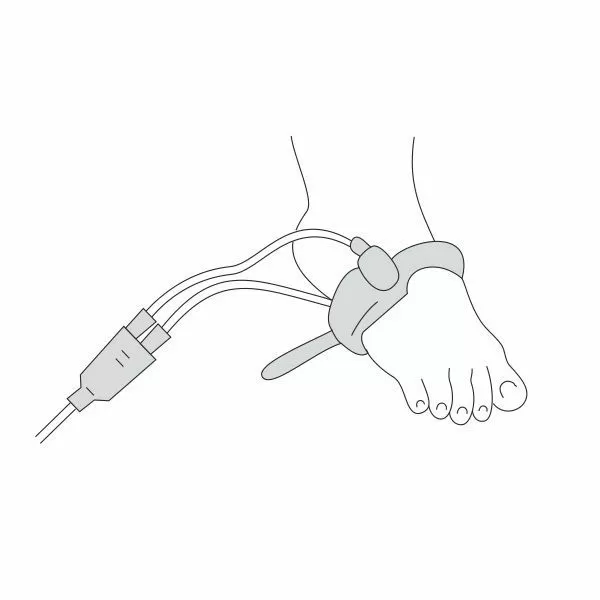

Почему может врать пульсоксиметр?

Причин, по которым пульсоксиметр может проводить измерения неверно, бывает несколько:

- у вас холодные руки. Согрейте их перед измерением;

- вы не до конца поместили палец внутрь прибора или измерению мешает длинный ноготь. Толстый слой гель-лака тоже может быть препятствием;

- вы долго находились в медицинской маске. Снимите ее, подышите глубоко и после этого делайте замер.